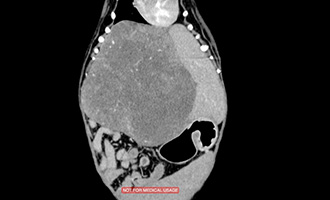

術前CT画像 |